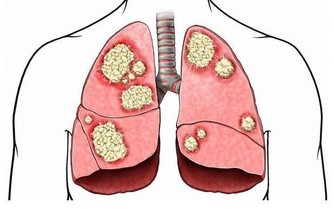

食物炸過後帶有反式脂肪,會阻塞血管、硬化動脈,不但會老化肌膚,還可能罹患心血管疾病。